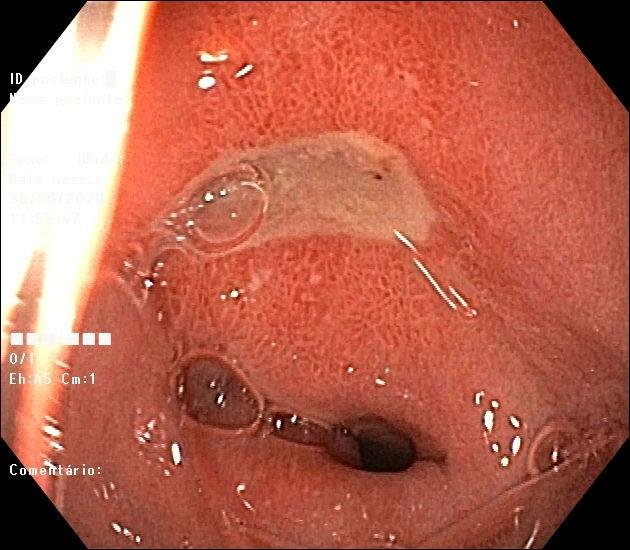

Úlcera no duodeno na endoscopia